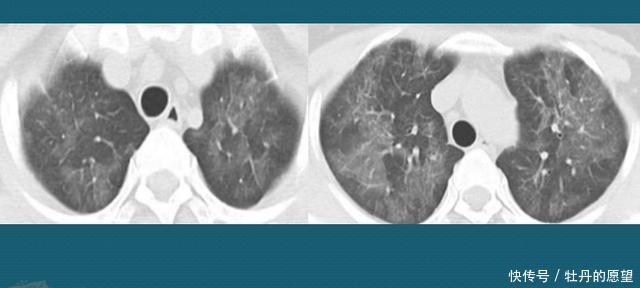

重磅!美国首例新冠病毒肺炎治疗康复全过程 | N

1080x863 - 67KB - JPEG